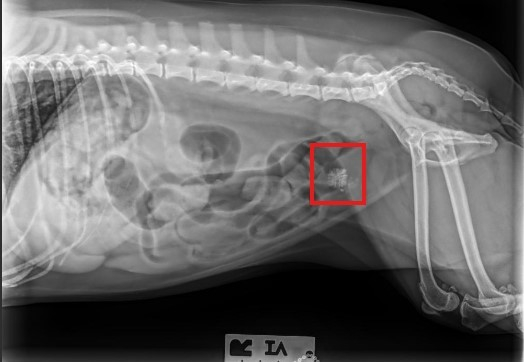

Onyx, a 6 yr old, Shih Tzu female spayed, dog presented for a routine exam and lab work. Elevated white and red blood cells, as well as large numbers of calcium oxalate crystals were identified in her urine. Antibiotics did not resolve this, and X-rays taken identified the presence of bladder stones. Medical management using a calculytic diet was attempted unsuccessfully. Surgery was subsequently performed and stones removed via a cystotomy.

Schedule an appointment with your veterinarian. Diagnosis requires a radiograph or ultrasound of the bladder. Your veterinarian will discuss medical and surgical treatment options based on your pet’s history, symptoms, the size, number and location of stones.